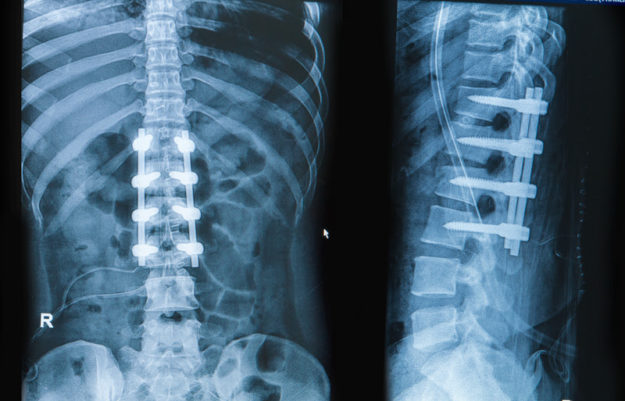

CUANDO UN PACIENTE TIENE CADERA Y DOLOR DE ESPALDA, ¿DE DÓNDE VIENE EL DOLOR? ¿DE LA CADERA? ¿DE LA COLUMNA BAJA? ¿DE AMBOS?

por Marc Darrow. En la Facultad de Medicina de la University of Washington, Departments of Orthopaedic Surgery and Neurology and Physical Therapy, los cirujanos y terapeutas querían examinar a los pacientes que tenían osteoartritis de cadera y/o deformidad de cadera para encontrar una relación con el dolor de espalda. El complejo espalda/ cadera…